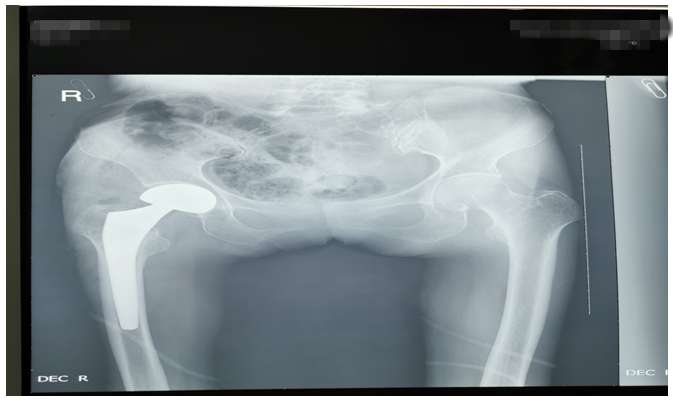

還有一位76歲鄧大媽,外傷致右側(cè)股骨頸骨折。外傷后因疫情鄧大媽一直未就診,在家非常痛苦,因疼痛不能平臥,一直坐位,臀部褥瘡形成,同時(shí)被骨折疼痛折磨地夜不能睡、不思飲食。鄧大媽基礎(chǔ)病較多,有高血壓病、腦梗塞、心臟病等病史,因骨折后時(shí)間長(zhǎng)、錯(cuò)位明顯,入院后積極治療內(nèi)科疾病,完善各項(xiàng)輔助檢查,在麻醉師及內(nèi)科醫(yī)師協(xié)助下,為鄧大媽成功行右側(cè)髖置換術(shù),手術(shù)順利。術(shù)后鄧大媽的臉上又有了笑容,夜間也能休息好了,術(shù)后第二天就開始下床活動(dòng),家屬看到自己的老母親恢復(fù)地這么好,非常滿意。(見下圖)

右髖正側(cè)位手術(shù)前后對(duì)比圖